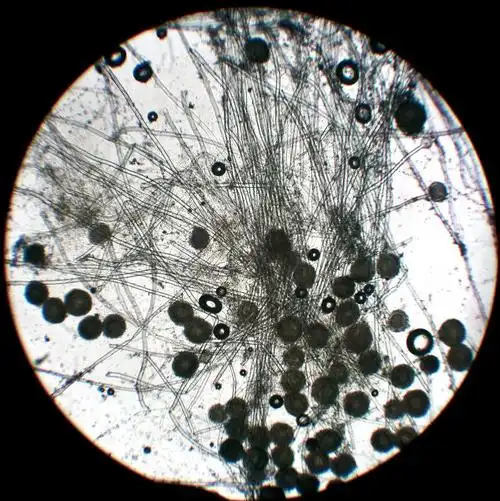

犬解剖结构与生理习性

犬 解剖结构与生理习性 课程名称:宠物疾病诊治.

犬解剖结构与生理习性ppt